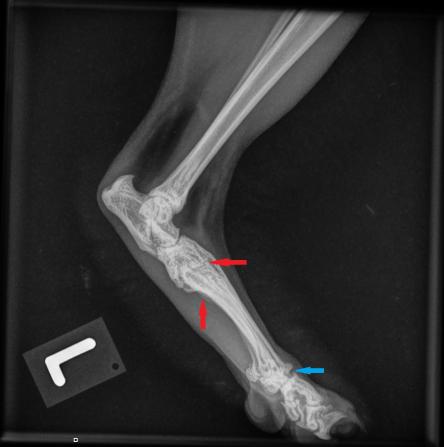

Die Besitzerin berichtet, dass der Kater recht lahmheitsfrei laufe, aber nicht über eine grosse Sprungkraft verfüge. Die Beine von Maxwell sind eher kurz und er scheint hinten und vorne X-beinig. Der Gang der Katze wirkt staksig; eine eigentliche Lahmheit ist nicht zu sehen. Um Aufschluss über die Situation in den Gelenken zu erhalten, werden die Vorderpfoten/Handgelenke, Hinterpfoten/Fusswurzelgelenke und die Wirbelsäule geröntgt. Es ist zu erkennen, dass Hand- und Fusswurzelgelenke gegenüber der Normalsituation eine X-beinigkeit (Valgisierung) aufweisen, an verschiedenen Stellen Anzeichen einer Arthrose vorhanden sind und insbesondere die Mittelhand- und Mittelfussknochen kurz und gedrungen erscheinen. Ein Teil der Fusswurzelknochen von Maxwell sind ausserdem zu einem einzigen Knochen verwachsen.